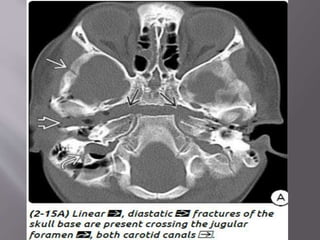

d) Diastatic Skull Fractures-fracture that widens

("diastases“ or "splits open") a suture or

synchondrosis. Diastatic skull fractures usually

occur in association with a linear skull fracture

that extends into an adjacent

suture.Sphenooccipital synchondrosis is most

common as , this suture doesn’t ossify till mid

teen.

b) Venous EDH- smaller, low pressure, develop

slowly

Most venous EDHs are caused by a skull fracture

that crosses a dural venous sinus and therefore

occur in the posterior fossa near the skull base

(transverse/sigmoid sinus) or the vertex of the

brain (superior sagittal sinus).

In contrast to their arterial counterparts, venous

EDHs can "straddle“ intracranial compartments,

crossing both sutures and lines of dural attachment

and compressing or occluding the adjacent venous

sinuses.